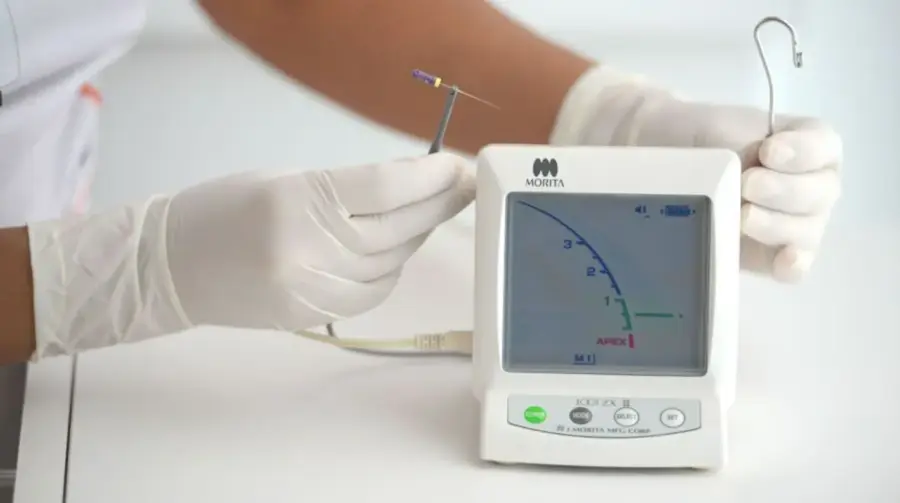

Công ty Anh & Em Morita Việt Nam